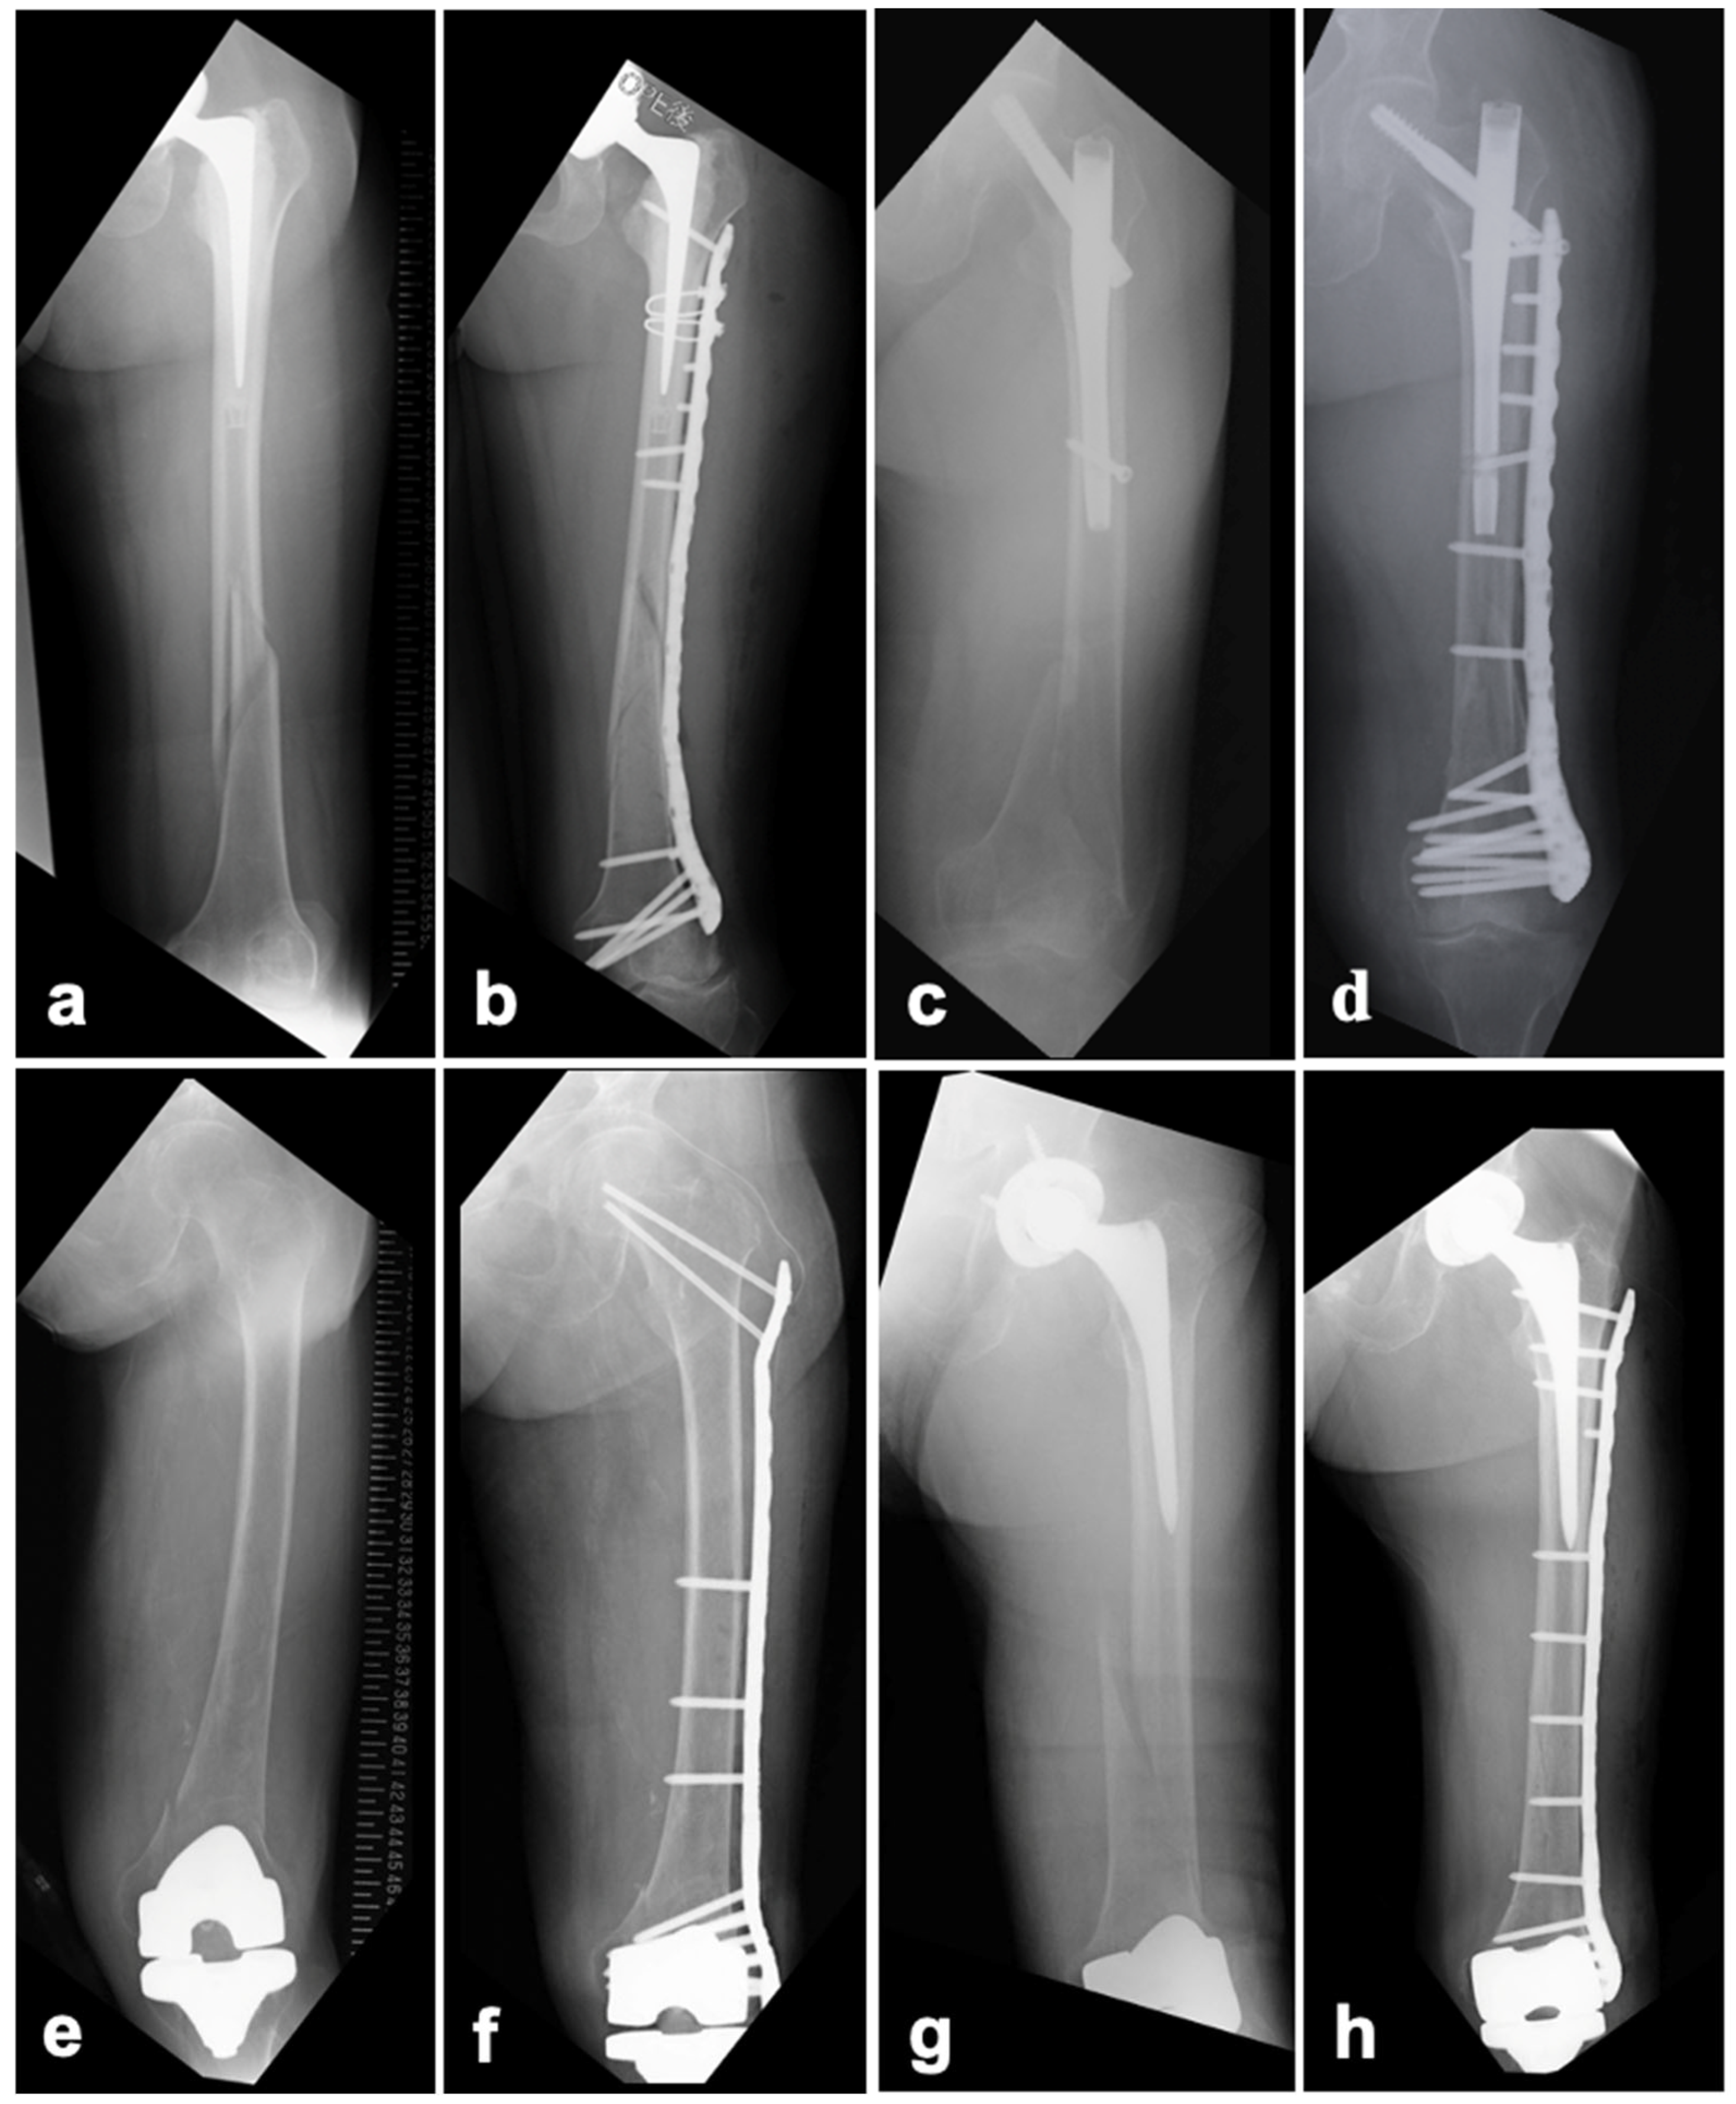

2.2. Preoperative Planning

2.3. Surgical Technique

2.3.3. TKA

3. Results